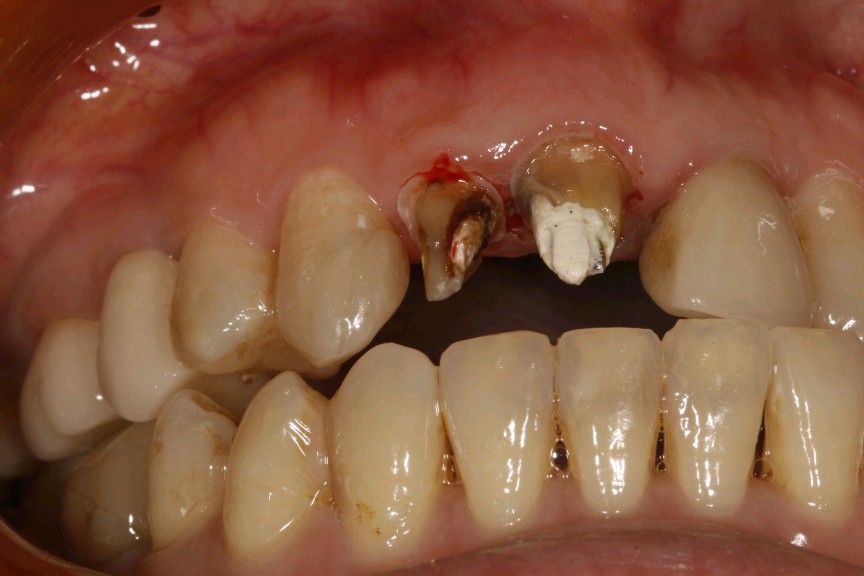

患者女,三十岁,11、12、21牙已行根管治疗,11、21烤瓷全冠修复。由于长时间烤瓷牙的佩戴,导致牙龈边缘发黑,颈缘处牙龈组织出现"黑线"。腭侧部分也出现了崩瓷的现象。对于这种情况,建议患者尽早重新修复,避免二次伤害。患者最终选择重新修复,也给出患者合理的方案,患者选全瓷冠修复,与今日佩戴完毕。边缘密合度良好,形态色泽自然美观,患者满意。

术中